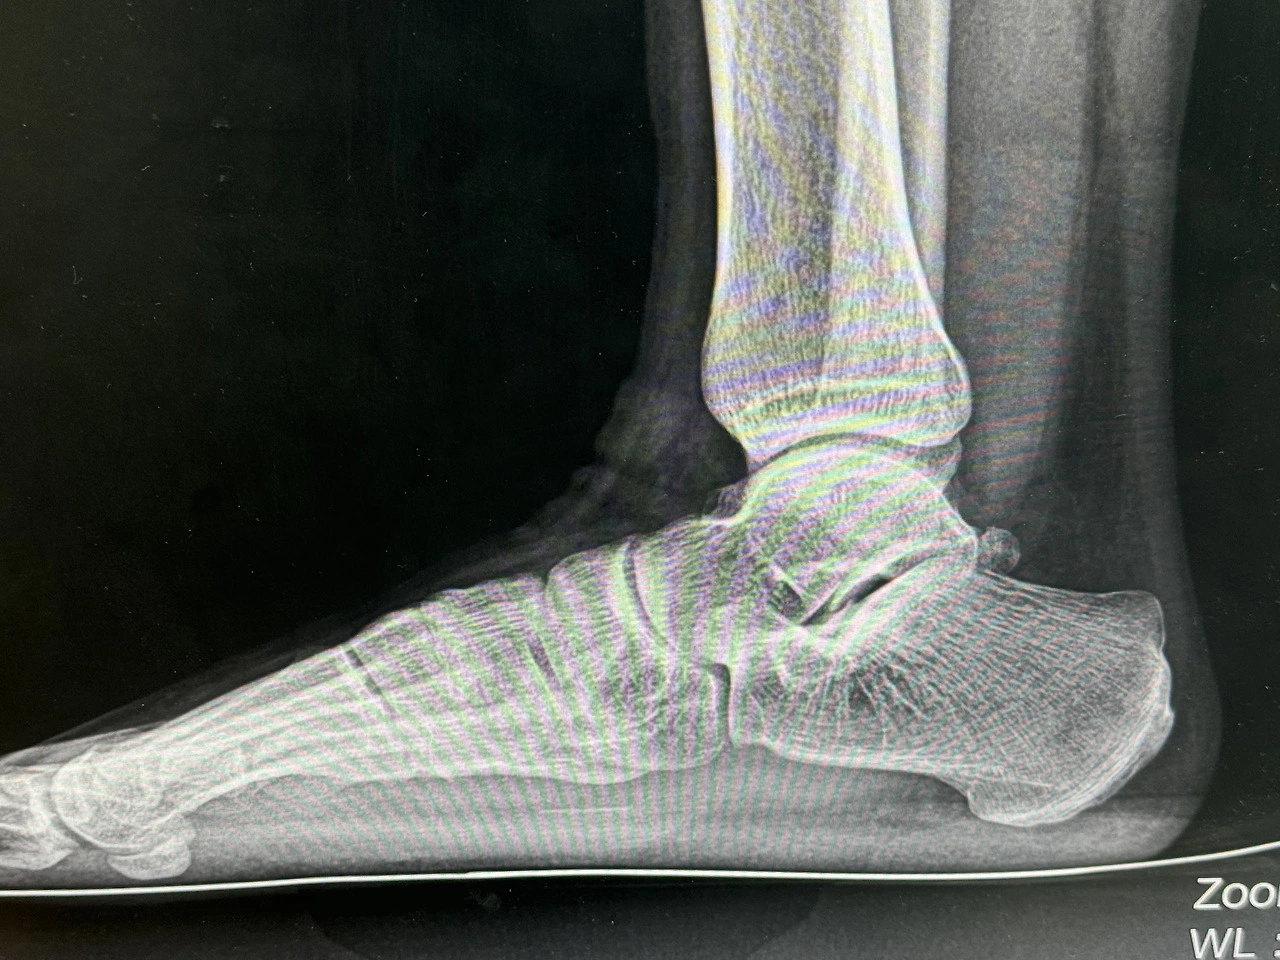

내 말목은 크게 다쳤다. 사고 지점에서 가까운 병원에서 1차 응급수술, 병원을 옮겨서 2차 본 수술 그리고 2번의 수술을 더했다. 그동안 마음고생이 많았다. 나 대신 본 수술을 할 병원을 알아봐 주고 나와 함께 구급차를 타고 이동해 준 누나, 내가 다친 날부터 내 다리가 괜찮아질 때까지 병시중을 들어준 아빠, 가게 일로 바쁜 나와 중에 항상 걱정해 주신 엄마. 나의 가족도 나와 같이 내가 다친 후로 항상 노심초사했을 것이다.

다친 후로 틈틈이 발목을 다친 것에 대해 보상받는 것들을 알아보았다. 내가 가지고 있는 얼마 되지 않는 보험에서도 사고 관련 보상이 있었다. 특히 국가 장해 등급을 받는 것에 관심이 갔다. 내가 해당이 된다면 어떤 것이라도 악착같이 받아서 그동안의 고생을 보상받고 싶었다.

국가 장해등급을 받으면 재 취업을 할 때에도 어느 정도 혜택이 있을 것 같았다. 만약 취업을 하고 회사에서 일을 하다가 계속 남아 있을 수 있는 후유증을 겪는다 해도, 회사에 굳이 설명 안 해도 장해등급이 있으면 회사가 어느 정도 이해할 수 있을 것이다. 여러모로 필요할 것 같아 여러 방면으로 알아보기 시작했다.

보험사에서 받을 수 있는 장해 보상금은 대체로 손해 사정사를 수배하여 계약하고 진행한다고 한다. 손해사정사가 모든 절차를 대행해 주고 수수료를 받는 방식이다. 여러 손해사정사와 컨텍 해 봤다. 내가 가입되어 있는 보험은 보상금이 크지 않아 대부분의 손해 사정사가 하려고 하지 안 났지만 몇 군데에서 하겠다는 연락을 받았다.

우선 손해사정사가 섭외한 병원에서 보상등급에 해당하는 검사 결과를 받은 다음 보험사에 청구해야 한다고 한다. 국가 장해 등급은 대부분 덤으로 해준다고 했다. 국가 장해 등급이 받기 어렵다고 생각해서 검사는 보험 보상금과 같이 해주는데 대신, 국가 장해등급을 받게 되면 100만 원을 지급해야 한다는 손해사정사도 있었다. 검사 비용은 30만 원 정도였다.

본 수술을 한 병원에 국가 장애 진단서를 써줄 수 있냐고 물어보았다. 마지막 수술에서 줄기세포를 넣어서 비용이 1000만 원이 나왔다. 물론 실비보험으로 90%는 커버되었다. 아빠가 실비를 들어놓지 않았다면 어떻게 되었을지 아찔하다. 그 외에도 어려 번의 수술을 진행했었기 때문에 당연히 써줄 거라 생각했다. 의사 선생님의 진료 때 국가 장해 진단서에 대해 물어보니 써본 적이 없어서 다른 의사 선생님께 물어보고 알려 주신다고 하셨다.

다음 진료 때 다른 의사 선생님 들게 물어보았는데 내가 장해등급을 받을 확률은 적다고 말씀하셨다. 일부러 안 써준다고 느끼기도 했고, 있는 그대로 말씀해 주신 것 같기도 하는 기분이 들어 헷갈렸다. 나는 그래도 써주실 수 있냐고 물으니 가져오면 써준다고 하셨다. 병원에 장해진단서 양식이 없는 것이 의문이었지만 일단 그냥 알았다고 했다. 종합적으로 생각해 왔을 때 이병원은 장해 진단서에 대해 부정적이라는 생각이 들었다. 써준다 해도 있는 그대로 써주지 않을 수도 있다는 생각이 들어 일단 본 수술을 한 이병원은 보류하기로 했다.